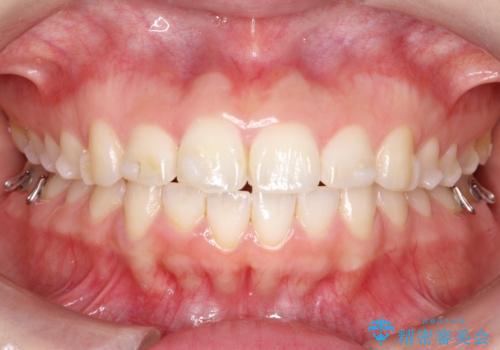

【インビザライン】前歯が出ているのを治したい

- 前歯が出ていることを主訴に来院されました。

前歯の突出感が改善され、満足していただきました。